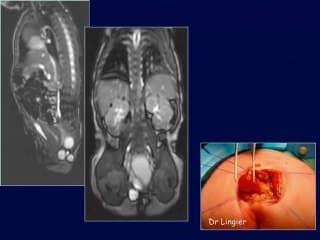

L'auteur précise l'apport de l'IRM dans l'affinement diagnostic des kystes abdominaux dépistés en échographie. De nombreux exemples des principales pathologies sont montrés : duplication digestive, lymphangiome kystique, kyste du cholédoque, kyste ovarien, pseudo kyste méconial etc..Son interêt parait incontournable dans les CPDPN avec une prise en charge thérapeutique optimale.